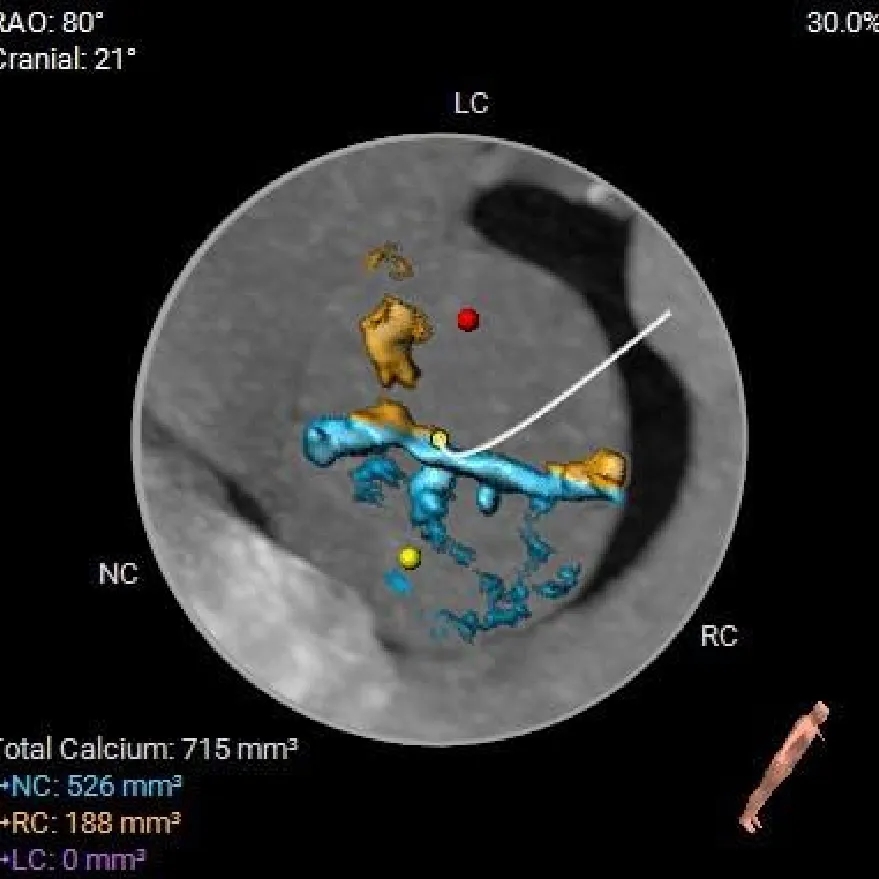

主动脉根部测量

Annulus

21.9mm

LVOT

22.3mm

钙化积分

715mm3

STJ

34.9mm

AAO

42.2mm

SOV

30.4mm*37mm

Type-0二叶瓣,中-重度钙化

瓣环径约21.9mm,敞口型流出道

冠脉风险评估

Left Coronary

LCA & Leaflet

Right Coronary

RCA & Leaflet

左、右冠脉高度尚可

双侧瓣叶不长

结合SOV、STJ内径评估冠脉风险不高